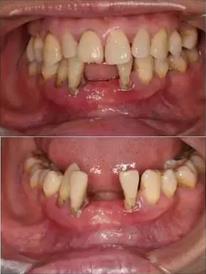

去除不良修復(fù)體后鄰牙松動(dòng)

拔牙后照片